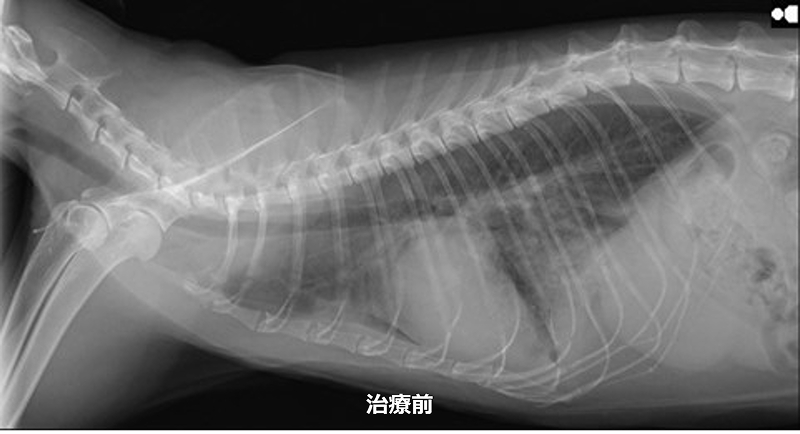

猫の心筋症 治療前と治療後

心筋症は心臓の壁が厚くなることで、心臓の中に十分に血液が入らなくなり、全身へ血液を上手く送り出せなくなります。早期の段階では、心臓が頑張って働くことにより全身に大き影響はありませんが、心臓が限界を迎えると心不全の状態となります。

病気がかなり進行するまでは、ほとんどの子で無症状です。心不全となり、肺水腫や胸水などにより呼吸が速くなったり、食欲が落ちたり、あまり動かずじっとしていることが多くなります。

また、心臓内で血液がうっ滞することにより、血栓が出来やすくなります。血栓は、肺や腎臓、足の血管に詰まります。腎臓につまると血尿が出たり尿が出なくなったります。足の血管につまると、足が急に動かなくなり激しく痛がることがあります。

心筋症の症例でも心臓に雑音が認められるとは限らないため、心臓の音が正常でも油断できません。そのため、中年齢になったら、定期的に心臓の検査を受けることをお勧めします。

心筋症は、手術で治すことは出来ないため、薬による内科治療で治すことになります。当院では、心臓超音波検査を行い治療薬を調整することで肺水腫や血栓症になるリスクを軽減することができます。

内科治療を行うことで、心筋症の進行をゆっくりにして心不全になるまでの時間を伸ばすことや、心不全の症状を和らげることが出来ます。また、心筋症の進行による血栓予防として抗血栓療法も行なっております。